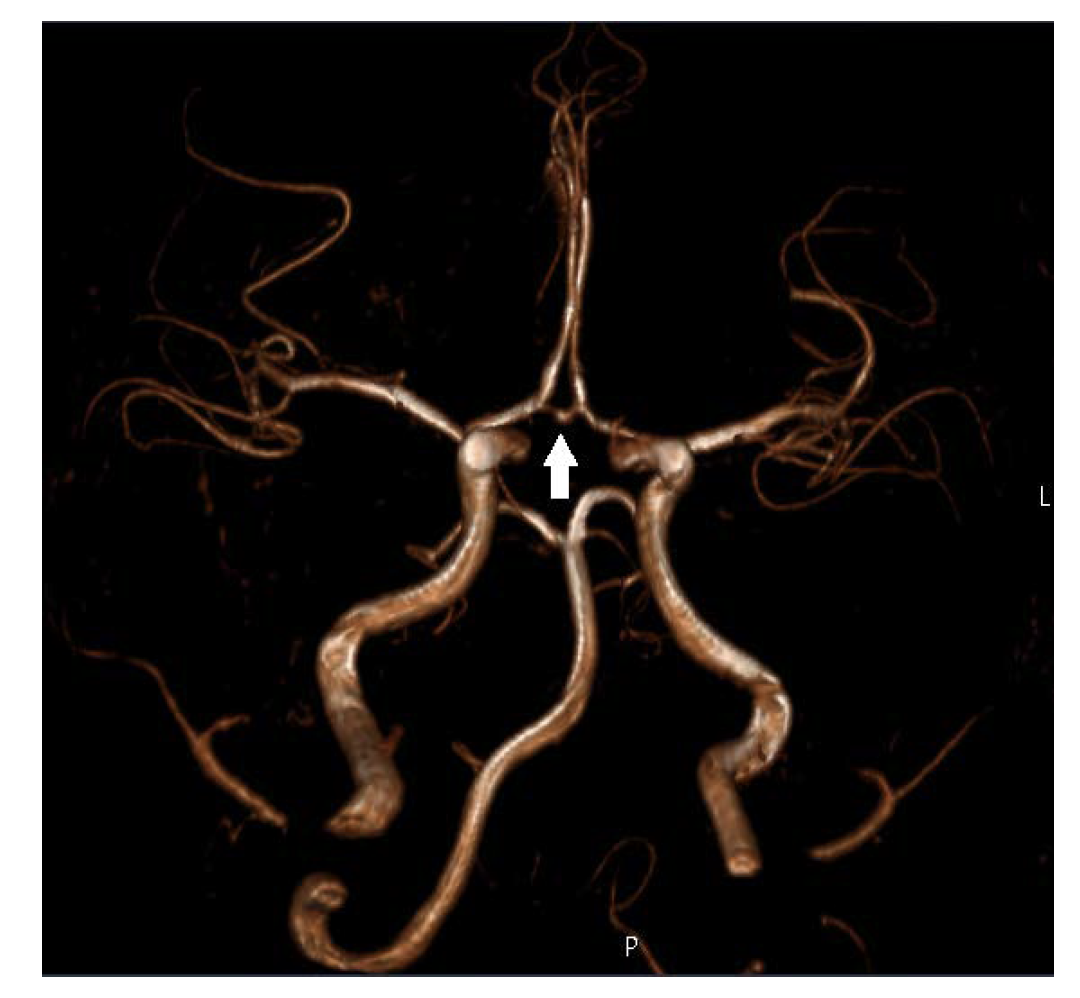

During follow-up the coronary ectasia did not regress and a CT angiogram was carried out, showing, in addition, the presence of giant coronary artery with no significant stenotic lesions. Further investigation showed dilatation of the proximal superior mesenteric artery and small fusiform dilatation of the anterior communicating artery (Figure 4). A treadmill stress test showed no signs of ischemia.